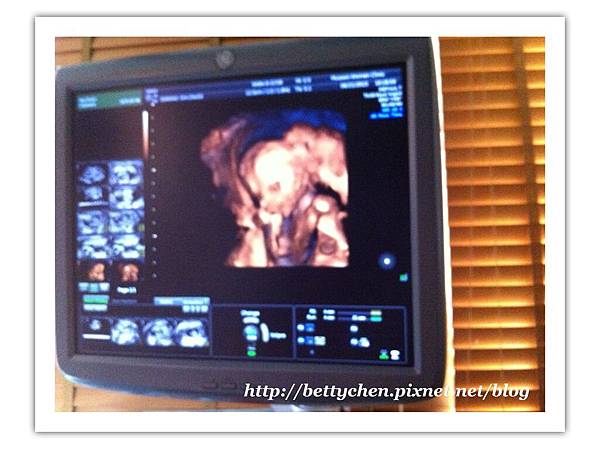

既然你都轉過來啦~~呵呵^^

林醫生特別照了4D給我看看你呢~~~

17

林醫生說小元寶手在上面,臉在下面~~~

叫我故意咳一下,看他會不會轉個方向~~~

哈哈^^好神奇呢~我咳了小元寶真的動了動....

18

小元寶臉露出來啦~~~

手一直揮來揮去~~~五官看得很清楚~~~

19

動不停的小元寶,頭手一直動~~~